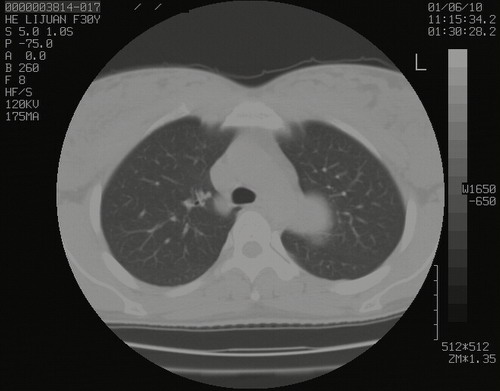

怀孕3个月时(2009-3至4月间),自述突感左侧前后胸疼痛1天,以前胸明显,随后偶感闷痛,余未见异

左肺尖脊柱旁沟肿块,境界清楚,边缘光滑,密度不均,内有多发点片状钙化,考虑良性肿瘤,骨软骨瘤或神经源性肿瘤可能,肺错构瘤不除外。

左后上纵隔见一类圆形肿块影,外侧边界清,密度不均匀,内可见点状钙化影,增强呈不均匀强化,考虑神经源性肿瘤可能。期待病理结果。